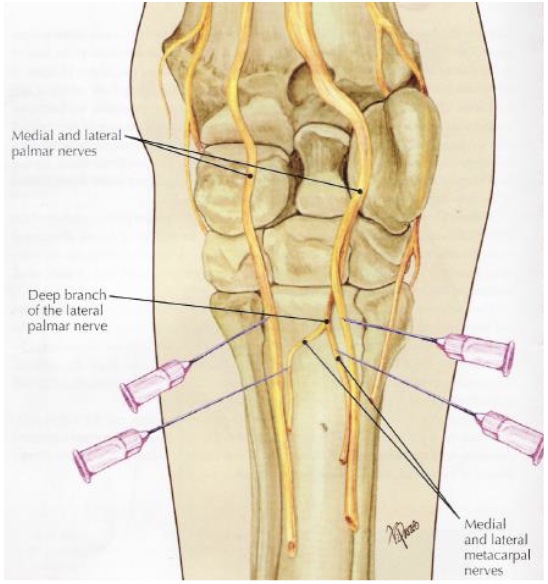

what is desensitized in a high 4 point nerve block (below carpus)

medial & lateral plantar nerves (DDFT & SDFT)

medial & lateral palmar metacarpal nerves (MC2, MC4, prox suspensory ligament & origin)

inferior check ligament